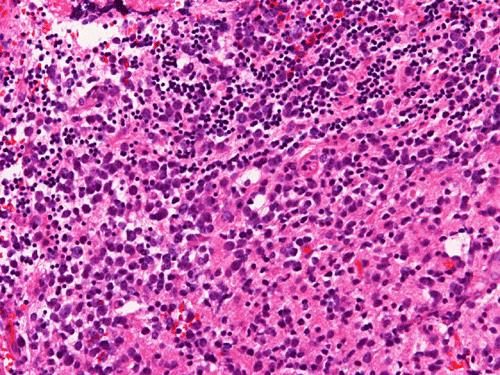

Permanent Sections:

The material for permanent sections is largely semi-liquid in consistency. There are only very few fragments of cerebellar tissue that are infiltrated by the tumor. The bulk of the diagnostic material are solid sheets of neoplastic cells (Panel G). The cytologic features are similar to what we have observed in the cytologic preparation  (Panel H). In essence, the tumor is composed of solid sheets of large polygonal and rather monotonous atypical cells with a thin rim of cytoplasm and molding which lead to a mosaic pattern. These features are consistent with lymphoma. On immunohistochemistry, practically all the neoplastic cells are positive for leukocyte common antigen (LCA) (Panel I), CD20 (Panel J) and many of them are positive for CD79a (Panel K). Only reactive T-cells but not the large, atypical cells are positive for CD3 (Panel L). The neoplastic cells are essentially negative for Bcl-6 (Panel M) but some of them are positive for Bcl-2 (Panel N). The large atypical cells are negative for kappa and lambda light chains on immunohistochemistry. There is no immunoreactivity in the neoplastic cells for cytokeratin (AE1/AE3), S100, pan-melanoma marker (Mart-1, tryptase, and HMB-45).

Similar to the systemic counterparts, diffuse large-B cell lymphomas of the CNS are characterized by large, pleomorphic lympyoid cells. Histologically, however, PCNSL shows the unique angiocentric infiltrating pattern, which is more prominent at the edge of the lesion. The tumor cells dissect and expand the perivascular network in a concentric manner which is best demonstrated by reticulin stain

[click here to see a picture]. Systemic DLBCL does not show this particular pattern of growth. The tumor infiltrates the brain parenchyma between blood vessels as small clusters and individual cells. Confluent areas of tumor may show necrosis, with residual viable tumor cells being found mostly around blood vessels. The boundary of the tumor may be relatively discrete, but it is more common for perivascular cuffs and single infiltrating lymphoma cells to be found at some distance from the tumor mass, extending far away from radiographically evident tumor margins. The malignant lymphocytes lack a cohesive appearance, do not form glands or other structures. The nuclei vary from round to indented or cleaved, and prominent nucleoli can be noted. The cells have only a small amount of basophilic cytoplasm. Variable numbers of mitotic figures and apoptotic cells are seen.